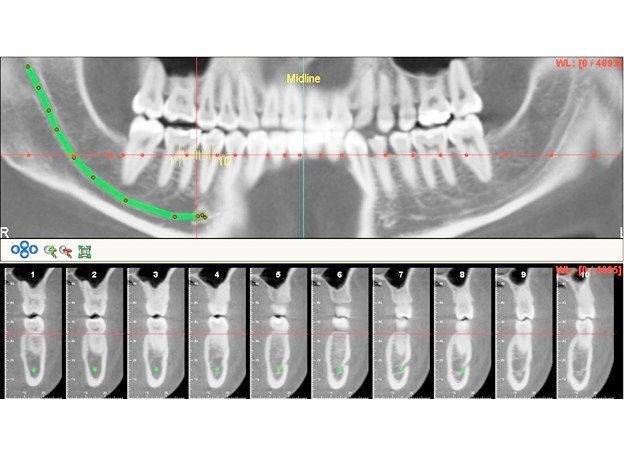

He is certified in Cone Beam Computed Tomography (CBCT) and has extensive experience in advanced radiological diagnosis. Dr. Singh is associated with several reputed centers across India as a consultant radiologist for CBCT reporting. His expertise includes implant planning, impacted teeth localization, oral and maxillofacial pathology interpretation, TMJ assessment, maxillary sinus evaluation, and airway analysis.

Single tooth CBCT 1000/-

Single tooth (If impacted or partially impacted) 1500/-

Quadrant CBCT 1500/-

Single arch CBCT 1800/-

Full Mouth CBCT 3500/-